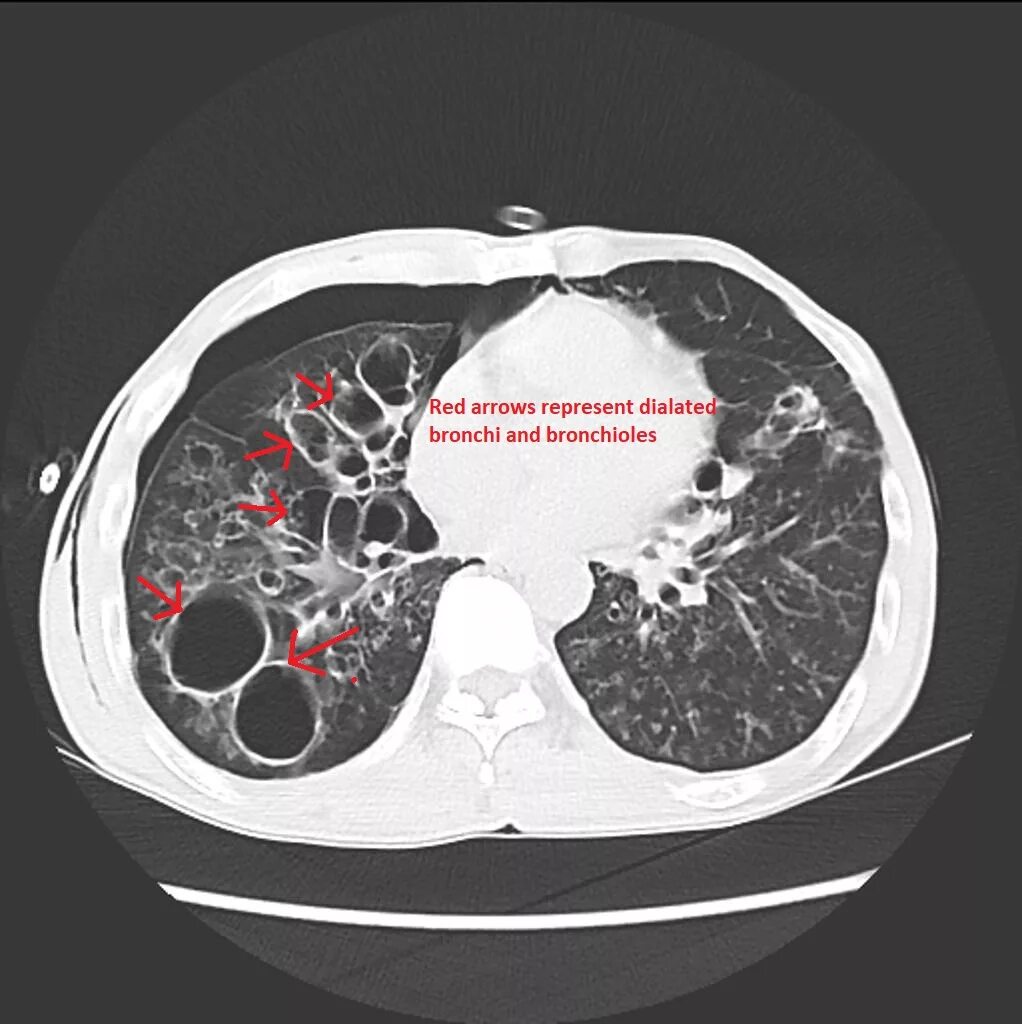

Фиброз кт